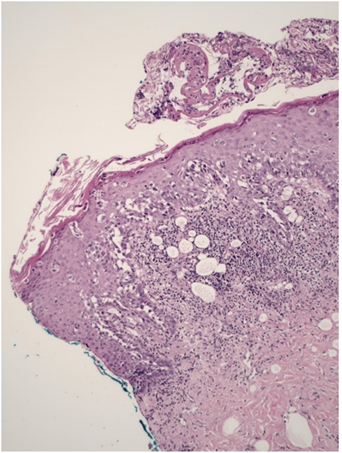

An incisional biopsy of the nipple revealed intraepithelial neoplasia with a pagetoid pattern, composed of clear vacuolated cells, consistent with Paget’s disease, associated with a focus of adjacent spongiotic dermatitis (Figure 2).

Figure 2: Anatomopathological examination (H&E, 100x): Intraepithelial proliferation of a pagetoid pattern consisting of large cells with clear cytoplasm, pleomorphic nucleus, and prominent nucleolus, compatible with paget's cells.